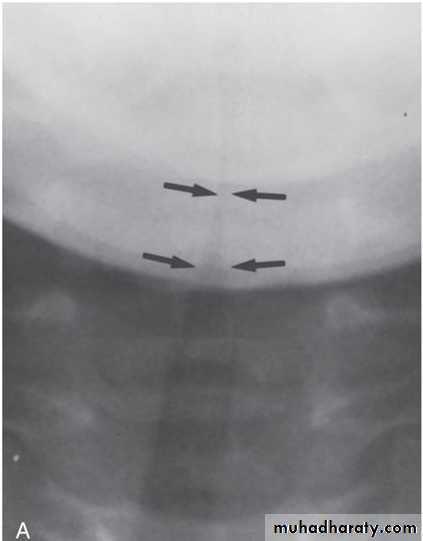

Q 10/ A previously healthy 2-year-old black child has developed a chronic cough during the previous 6 weeks. He has been seen in different emergency rooms on two occasions during this period and has been placed on antibiotics for pneumonia. Upon auscultation, you hear normal breath sounds on the left. On the right side, you hear decreased air movement during inspiration but none upon expiration. Inspiratory (A) and expiratory (B) radiographs of the chest are shown below. Which of the following is the most appropriate next step in making the diagnosis in this patient?

A

B

Recurrent pneumonias in an otherwise healthy child should suggest the potential for anatomic blockage of an airway. In the patient in this question, the findings on clinical examination suggest a foreign body in the airway. Inspiratory and expiratory films can be helpful. Routine inspiratory films are likely to appear normal or near normal (as outlined in the question and noted in the first radiograph). Expiratory films will identify air trapping behind the foreign body (as noted on the second radiograph). It is uncommon for the foreign body to be visible on the plain radiograph; a high index of suspicion is necessary to make the diagnosis. Suspected foreign bodies in the airway are potentially diagnosed with fluoroscopy, but rigid bronchoscopy is not only diagnostic but also the treatment of choice for removal of the foreign body.